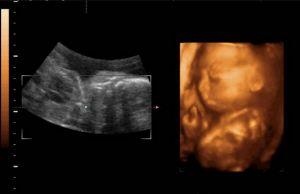

生儿子的四维彩超图片

现在很多人,都会想提前预知胎儿的性别。除了提前抽血做DNA检测,另一个就是通过四维彩超来判断。但是,虽然四维彩超的准确性已经相对较高,出现四维翻盘的概率也还是有的。小编就曾听说过邻居的一个故事,连续生了两个女儿之后,一心求男,但很遗憾的是四维彩超被告知是女孩。家人犹豫再三,本来舍不得打掉,后面又觉得生太多女儿是个累赘,结果在孕妇八个多月的时候才去引产。可等孩子打下来,竟然是男孩,并且还挣扎动弹了几下才死去,一家人全线都晕了过去。虽然,一家人信誓旦旦地要去揍B超医生,可是事已至此,又有什么可以挽回的呢?

一般来说,四维被告知是女宝但是生下来却是男宝,四维翻盘的可能是有的,原因就在于性器官判断错误。在孕22-26周的时候,胎儿的性器官已经发育得很好了,再加上四维彩超的清晰程度,一般就可以直接看出男女。但如果由于一些特殊的原因,导致误判,那就会出现翻盘的现象。通常,原因可能有如下3个:

原因一、JJ和脐带产生混淆

在妈妈的子宫里,脐带既是母体向胎儿输送营养的营养通道,同时也是胎宝宝的玩具,胎儿很喜欢握着脐带。做四维彩超的时候,因为胎儿是左右翻滚的,有时候医生怎么引导都不肯转过头来,坚持面向着妈妈。这样,医生在看到小JJ时,就很容易因为看不清楚而将JJ看作是胎儿的脐带。

原因二、JJ刚好被手挡住

虽然说四维彩超已经相对清楚,但受到羊水和一些组织液的影响,有些部位依然没法看得很清楚,比如胎儿的耳朵,就不在筛查范围内,因为真的很难看清楚。四维彩超时,虽然医生有意观察胎儿的性器官,但如果胎宝宝比较淘气,用手遮住了性器官,并且胎儿的手指和JJ是比较相像的,看错就难免了。

原因三、JJ被胎儿双腿夹住

胎儿在妈妈的子宫里头,各种姿势都是可能出现的。如果做四维彩超时,胎儿的双腿恰巧就夹住了JJ,那么看不到JJ的医生就会误以为这是一个女宝。有些时候,医生会用B超的探头引导宝宝左右翻滚,看看能不能从不同的角度进行判断。那如果就是那么刚好,各个角度的姿势都是挡住了JJ,那就会导致医生判断错误了。

不管是四维彩超还是准确度更高的DNA抽血测试,误差都是存在的。四维彩超主要是依靠彩超医生根据自身的专业,结合B超影像做出的一个判断,存在一定的主观性。并且,这个鉴定的过程也是需要胎儿的配合的,有些时候并不就那么刚刚好。更好的办法就是顺其自然,不要抱着严肃的心态提前去预测男女,用娱乐的心态去看看肚子形状、尿液的酸碱度等来推测男女是可以的,但如果将是否男女作为胎儿是否留下的依据,就真的是大大的没必要了。

以上就是与生儿子的四维彩超图片相关内容,是关于四维彩超的分享。看完b超单有这个一般是女孩后,希望这对大家有所帮助!